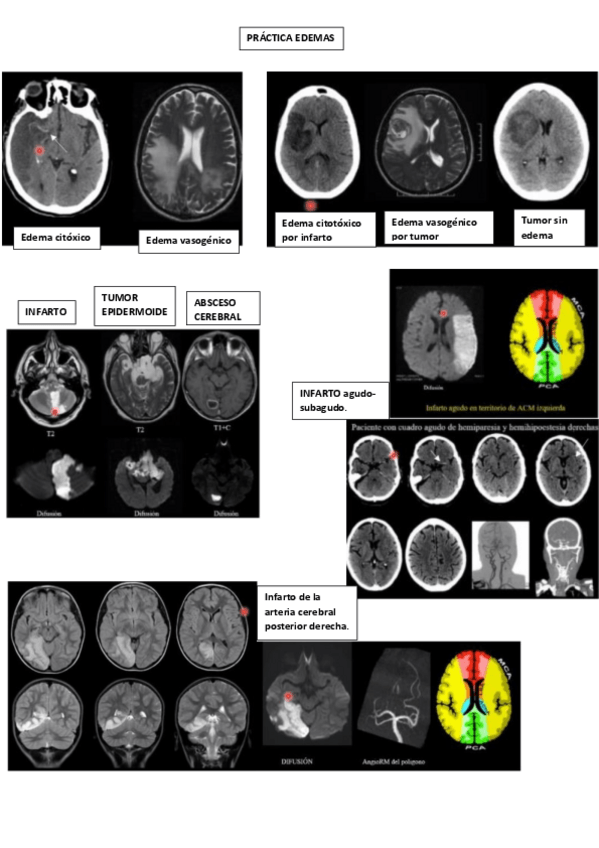

Practicas-SNC-II-Tumores-Infeccion.pdf